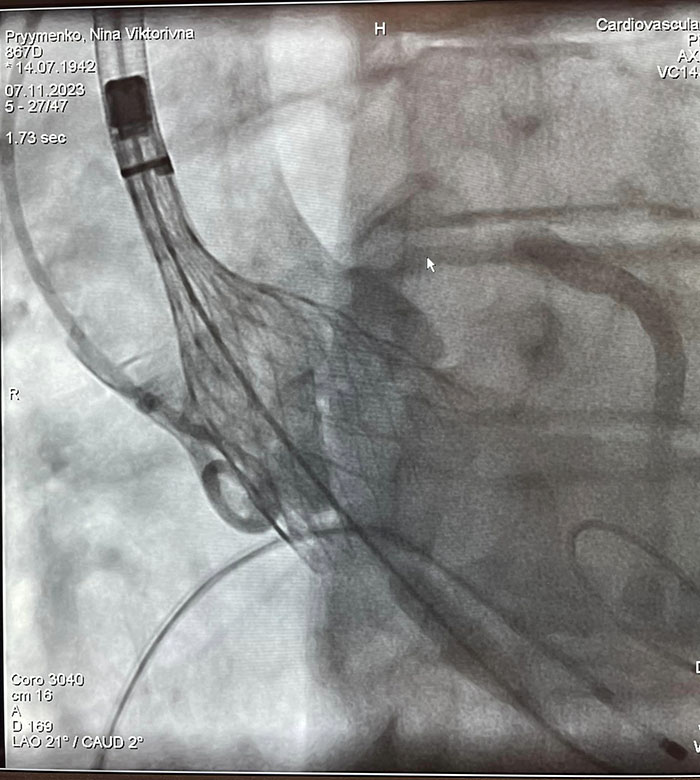

"В рамках цієї операції біологічний аортальний клапан, який закріплений на кінчику катетера, просувається до серця та закріплюється на місці аортального клапана, - йдеться у повідомленні. - Перевага: не потрібно проводити стернотомію грудної клітки, також немає потреби у використанні апарату для штучного кровообігу, немає наркозу, немає реабілітації".

Операції проводились бригадою медиків у складі Узун Д.Ю., Журавльов М.В., Бабкіна Н.А., Муравський Є.А., під прокторством Дітківського І.О. завідувача відділення: рентген-ендоваскулярних методів лікування вроджених та набутих вад НІССХ ім. М.М. Амосова.